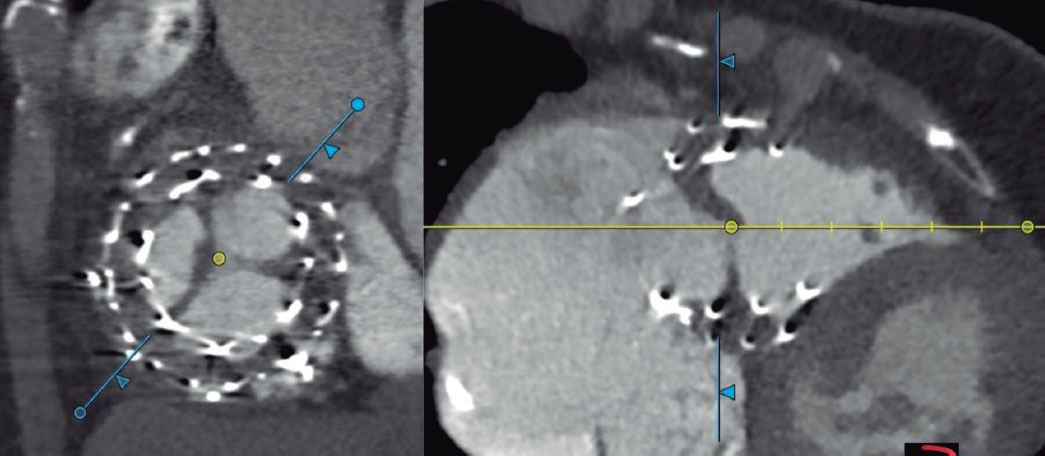

Las complicaciones precoces (30 días) tras la intervención se resumen en la tabla 2. Como complicaciones y datos reseñables, la paciente número 1 presentó insuficiencia mitral funcional grave 5 días después del implante de la válvula EVOQUE en posición tricuspídea (previamente tenía insuficiencia mitral funcional leve-moderada), que se resolvió volviendo a su basal tras la administración de levosimendán y tratamiento diurético intravenoso. El paciente número 3 (con bloqueo de rama derecha previo) desarrolló un BAV completo el tercer día tras el procedimiento, que precisó el implante de un marcapasos monocameral con cable en el seno coronario, sin incidencias. Los pacientes 3 y 4 presentaron fallo del ventrículo derecho transitorio que precisó dobutamina y vigilancia estrecha, en ambos casos resuelto con tratamiento médico en pocos días. La paciente número 8 presentó, en la TC realizada al mes del alta, una trombosis de prótesis que se confirmó con ecocardiografía transesofágica (figura 3); no presentaba dicha complicación en la ecocardiografía previa al alta. En la paciente número 10 también se detectó trombosis de prótesis en la TC de seguimiento al mes del procedimiento, igualmente confirmada por ecocardiografía. En ambos casos, la trombosis cursó de forma asintomática y en la actualidad las pacientes están en tratamiento con heparina no fraccionada.

Figura 3. Trombosis de velo anterior de prótesis EVOQUE (Edwards Lifesciences, EE.UU.).

Otro aspecto relevante es el tratamiento antitrombótico tras el implante de la prótesis. En nuestra serie, 1 paciente presentó trombosis de la prótesis EVOQUE en la TC de control al mes del procedimiento; en la ecocardiografía de control previa al alta no se visualizó ningún trombo y el gradiente transprotésico era normal (2 mmHg). Esta paciente fue dada de alta con rivaroxabán 20 mg, que ya tomaba previamente. La otra paciente que presentó trombosis de la prótesis estaba en tratamiento con acenocumarol por ser portadora de una prótesis metálica, con INR (International Normalized Ratio) en rango entre 2,5 y 3,5. En ambos casos, el tratamiento fue anticoagulación con heparina de bajo peso molecular. En el primer caso, en la ecocardiografía transesofágica realizada 1 semana después persistía la trombosis; el segundo caso tiene pendiente la ecocardiografía de control. Es interesante señalar que en el estudio TRISCEND II13 se recomendaba anticoagulación con warfarina (INR 2,5-3,5) u otro anticoagulante, y antiagregación con ácido acetilsalicílico durante 6 meses. En nuestro centro, el protocolo requiere mantener únicamente la anticoagulación que tomaba previamente el paciente (todos ellos tenían indicación de anticoagulación crónica), sin antiagregación. En el único paciente sin anticoagulación basal se realizó tratamiento con ácido acetilsalicílico. Por otro lado, los 2 casos de trombosis de prótesis en nuestro centro se diagnosticaron por TC, que no se realizaba según el protocolo del estudio TRISCEND II13, por lo que no se puede descartar que pasara inadvertida alguna trombosis subclínica. Si esto tiene relevancia en el seguimiento, en términos de una degeneración protésica precoz, es algo que tendrá que estudiarse en el futuro. Se considera que es necesario realizar una TC en estos pacientes con tratamientos percutáneos novedosos para valorar anatómicamente el resultado con mayor exactitud, así como para descartar complicaciones que puedan pasar desapercibidas con otras técnicas de imagen.

En cuanto al resultado hemodinámico tras el implante de la prótesis, fue óptimo en términos de reducción de la IT. El gradiente transprotésico máximo fue de 4,8 mmHg en nuestra serie, en con- cordancia con los valores bajos comunicados en TRISCEND II13, lo que indica una adecuada función hemodinámica de la válvula en ambas cohortes. Esto respalda la capacidad de la prótesis EVOQUE para ofrecer un desempeño valvular eficiente con una baja resistencia al flujo. Cabe destacar que en el caso de trombosis de prótesis diagnosticado por TC el gradiente transtricuspídeo por ecocardiografía era de 2 mmHg, lo cual resalta la utilidad de la TC en el seguimiento inicial de estos pacientes, ya que de otra forma podrían pasar inadvertidas trombosis subclínicas.